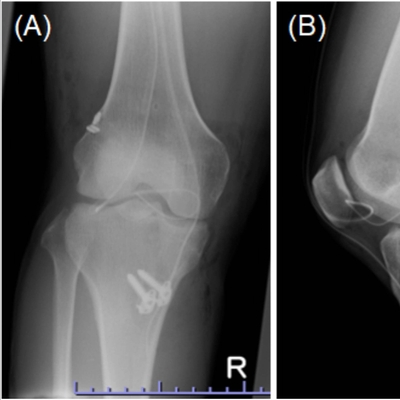

Click on an image below to view more info.